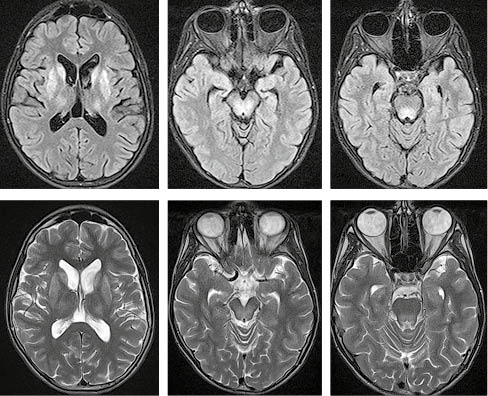

При виконання МРТ-дослідження головного мозку пацієнта виявлено типові ознаки хвороби Вільсона у вигляді підвищення МР-сигналу від головок хвостатих ядер, лушпин, блідих куль та таламусів в режимах Т2/Flair і Т2. Також наявне підвищення сигналу від покришки середнього мозку й дорзальних відділів моста (рис. 3).

/images/nn262-1672123r3_.jpg)